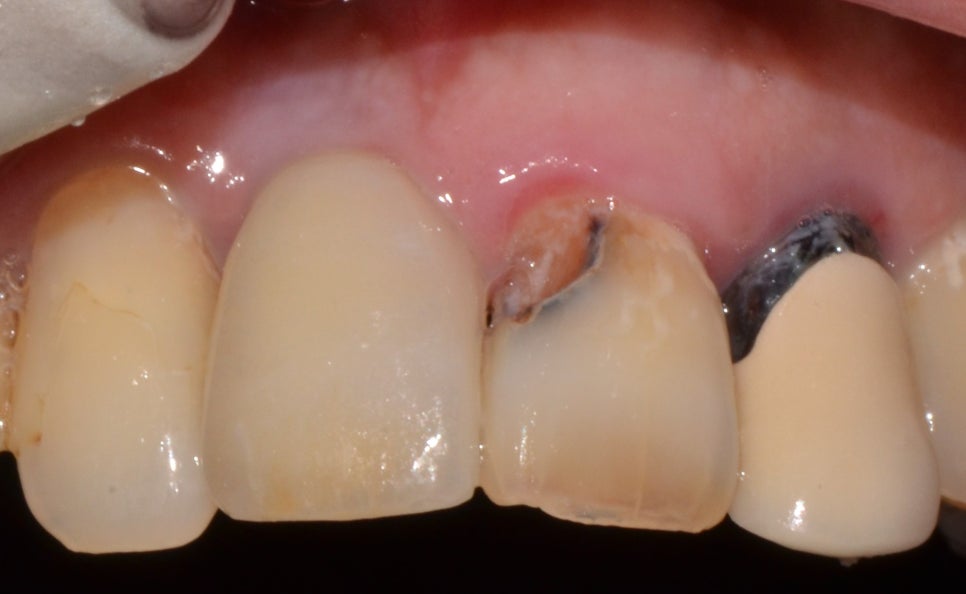

치료 전

2023년 2월 20일

내원 이유

오늘 같이 알아볼 환자분은 앞니의 흔들림으로 인해 통증이 있으면서 불편함을 느끼셔서 내원을 해주셨는데요. 50대 남성분이셨고 식사를 하고 음식을 씹을 때마다 아프다고 말씀해 주셨습니다. 3D CT로 구강 내부를 확인한 후 잇몸뼈의 상태 및 현재 구강 상태를 설명드린 후 임플란트 치료와 염증 치료를 같이 진행하는 것을 말씀드렸습니다.

좌측 상악 전치와 측절치 발치를 한 후 염증이 심한 케이스이기 때문에 발치를 하고 난 후에 3개월 정도는 염증 치료를 진행하였습니다. 그리고 임플란트를 식립해 주었는데요. 염증으로 인해 잇몸뼈의 상태가 좋지 않아 잇몸뼈 이식도 진행하였습니다. 발치를 하고 나서는 임시 틀니를 사용할 수 있도록 해드렸으며 염증이 우선적으로 개선되어야 했기 때문에 구강관리에 대한 설명을 드리고 현재는 많이 개선된 상태입니다.